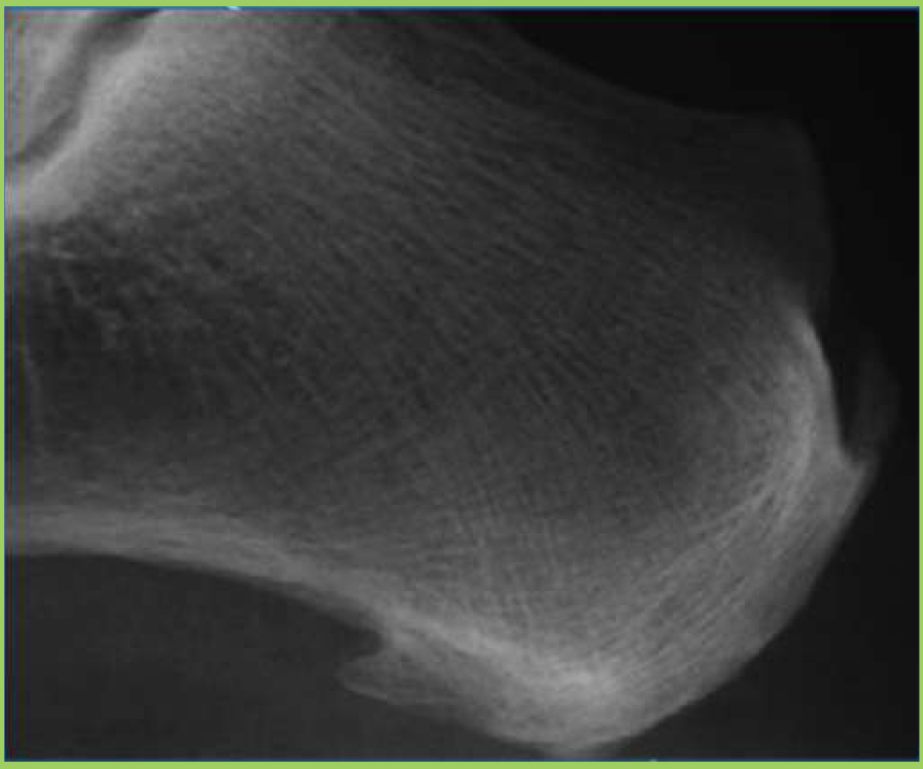

What two things are found on this image

achilles tendon enthesophyte

plantaraponerosis enthesophyte